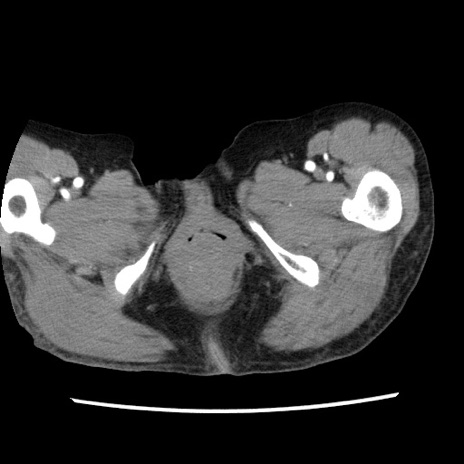

症例1(横断像)

【症例】80歳代女性

【主訴】腹痛

【現病歴】8時間前から腹痛あり来院。

【既往歴】糖尿病、脂質異常症、子宮体癌にて子宮全摘術

【身体所見】意識清明・会話良好だが腹痛で苦悶様、全腹部にわたって反跳痛と圧痛あり

【データ】WBC 13600、CRP 0.14、LDH 224、CK 90